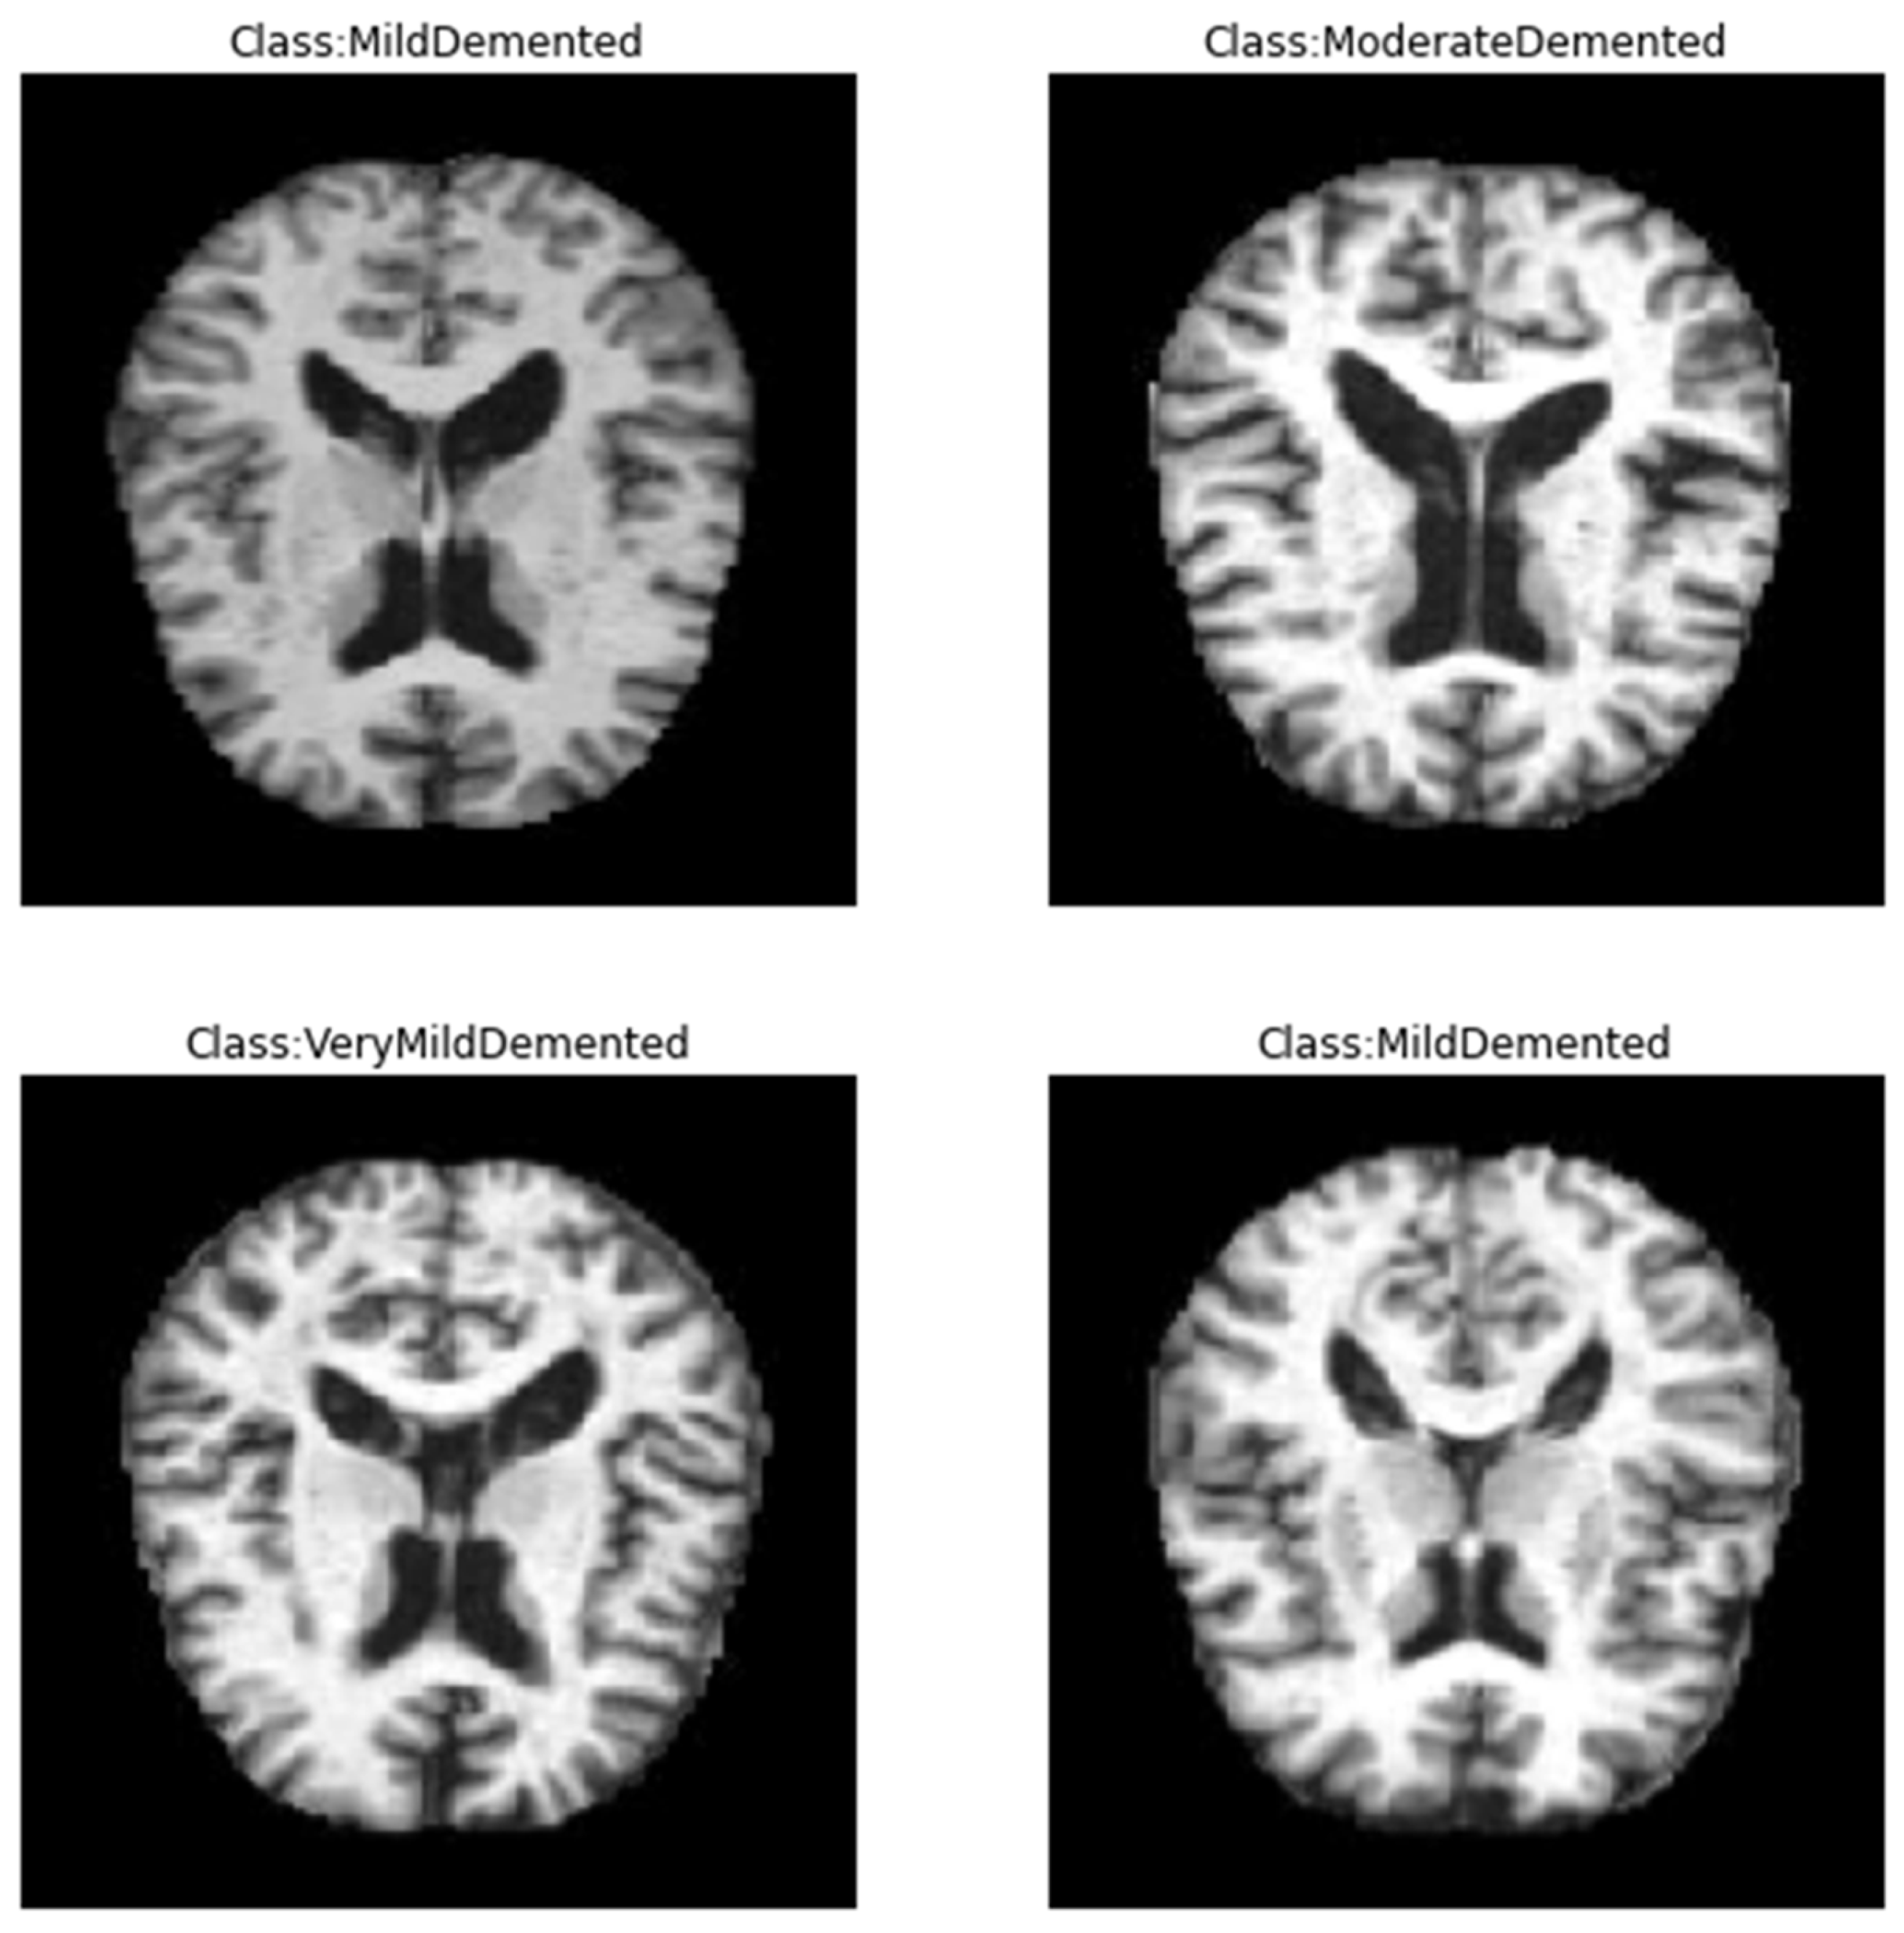

In this study, we employed the Alzheimer’s dataset [29], which is a hand-collected dataset consisting of MRI images that have been verified and labeled by experts. The data includes four different classes of images: Mild Demented, Moderate Demented, Non-Demented, and Very Mild Demented. These images can be used to train and test deep learning models aimed at accurately predicting the stage of AD. The dataset provides an opportunity for researchers and practitioners to develop algorithms that can accurately diagnose AD and aid in the development of effective treatments. With the growing global burden of AD, this dataset could play an important role in advancing our understanding of the disease and improving patient outcomes. The dataset is available on Kaggle and can be easily accessed, unlike other datasets, which are difficult to access. By making this dataset publicly available, the creators aim to encourage more research in the field and support the development of better algorithms for the diagnosis and treatment of AD. We employed this dataset as it is totally free, available with different classes, and small in size on a hard disk, unlike other common datasets in this field. Figure 1 shows samples of the dataset for the different classes. Table 2 shows the distribution of the records in the dataset, and Figure 2 shows the statistics of this dataset. Furthermore, a comparison between this dataset and other common datasets in this field is shown in Table 3.

Figure 1.

Sample of the data from Kaggle database [29].